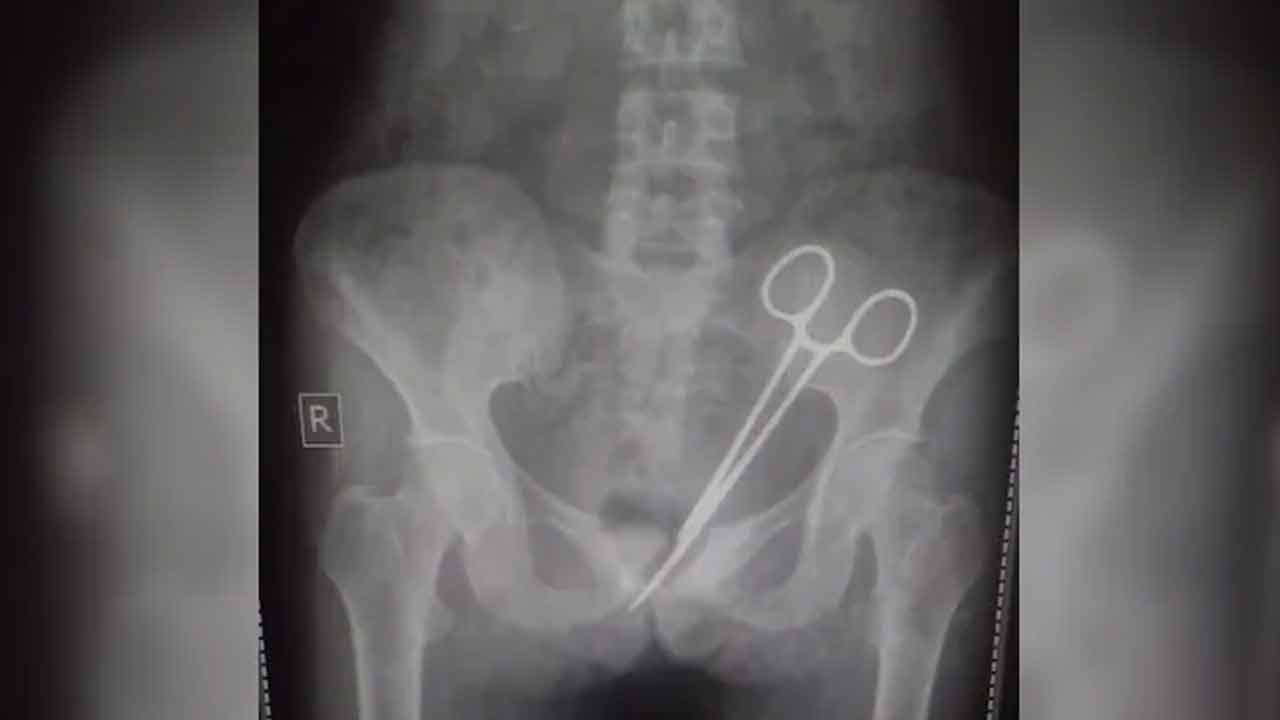

క‌డుపు నొప్పి మ‌రింత తీవ్రం కావ‌డంతో చేసేదేమీ లేక ఈ ఏడాది అక్టోబ‌ర్ 8న స‌ర్ తుటుబ్ న‌మ్‌గ్య‌ల్ మెమోరియ‌ల్ ఆస్ప‌త్రికి ఆమెను తీసుకెళ్లారు. అక్క‌డ బాధిత మ‌హిళ‌కు స్కానింగ్ నిర్వహించ‌గా, పొత్తి క‌డుపులో క‌త్తెర( Scissors ) ఉన్న‌ట్లు వైద్యులు( Doctors ) నిర్ధారించారు. దీంతో ఆవిడ‌కు స‌ర్జ‌రీ( Surgery ) నిర్వ‌హించి క‌త్తెర‌ను తొల‌గించారు.

అయితే ఆమెకు 12 ఏండ్ల క్రితం అపెండిక్స్( Appendix ) నొప్పి వ‌చ్చింది. దీంతో స‌ర్ తుటుబ్ న‌మ్‌గ్య‌ల్ మెమోరియ‌ల్ ఆస్ప‌త్రి వెళ్ల‌గా, వైద్యులు శ‌స్త్ర చికిత్స నిర్వ‌హించారు. స‌ర్జ‌రీ అనంత‌రం ఆమె పొత్తి క‌డుపులోనే క‌త్తెర మ‌రిచి కుట్లు వేశారు. ఇక అప్ప‌ట్నుంచి ఇప్ప‌టి వ‌ర‌కు ఆమె క‌డుపు నొప్పితో బాధ‌ప‌డుతూనే ఉంది. చివ‌ర‌కు ఆ క‌త్తెర‌ను తొల‌గించారు వైద్యులు. ప్ర‌స్తుతం బాధిత మ‌హిళ ఆరోగ్య ప‌రిస్థితి నిల‌క‌డ‌గా ఉంద‌ని వైద్యులు తెలిపారు.